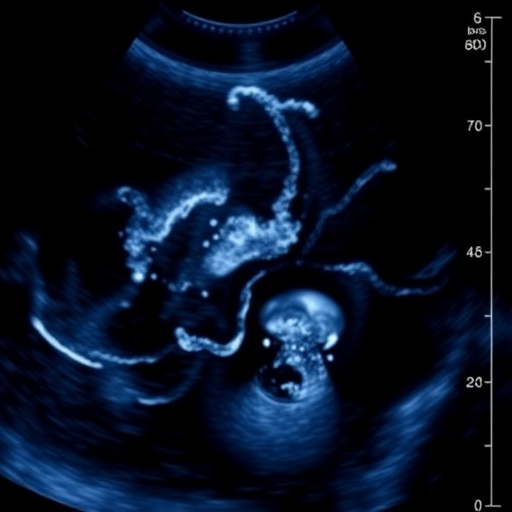

In a groundbreaking development poised to transform neonatal cardiology, researchers have unveiled a pioneering approach to the assessment of patent ductus arteriosus (PDA) using echocardiography, urging the medical community to move beyond conventional diameter-based criteria. This novel initiative promises to refine clinical trials and optimize early therapeutic interventions, as detailed in a recent publication in the Journal of Perinatology. The implications of this advancement are vast, addressing longstanding challenges in the diagnosis and management of PDA, a congenital condition predominantly affecting preterm infants.

Traditionally, the identification and treatment candidacy for PDA have hinged on measuring the ductal diameter through echocardiographic techniques. While this metric has served as a cornerstone in neonatal cardiology, experts have increasingly recognized its limitations, particularly the inability of diameter alone to accurately predict hemodynamic significance or clinical outcomes. The newly proposed framework incorporates a multifaceted echocardiographic assessment that extends beyond mere anatomical measurement to capture functional and physiological parameters critical in early PDA management.

From a technical standpoint, the transition to a multi-parametric echocardiographic assessment represents an evolution in neonatal imaging technology. Advances in Doppler modalities, higher-resolution transducers, and real-time three-dimensional imaging enable more precise measurement of cardiac structures and flow dynamics. These innovations facilitate detailed examination of the ductus arteriosus and its physiologic consequences, providing clinicians with actionable data that inform therapeutic decisions.